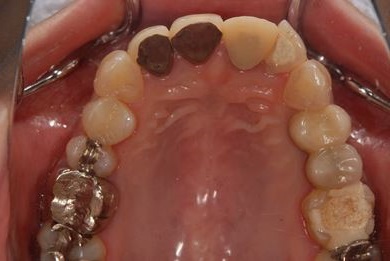

セラミックの症例写真 SHINBI

セラミック治療

| 治療内容 | オールセラミック4本(オールセラミック用土台4本)、メタルボンドセラミック2本(メタルボンドセラミック用土台2本) | ||||||||||||||||||||||||||||||||